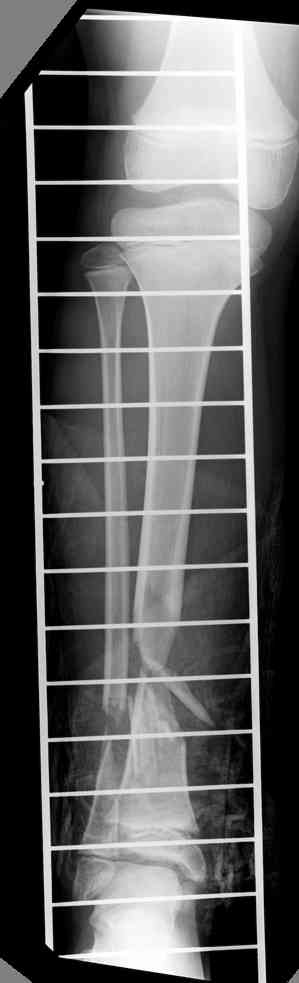

Пациент 19 лет, производственная травма, придавлен тяжелой плитой. Политравма (ISS 21).

1 - рентгенограмма (прошу прощения за качество) при поступлении;

Произведено ПХО, acute shortening (5 см), фиксация стержневым аппаратом Hoffman.